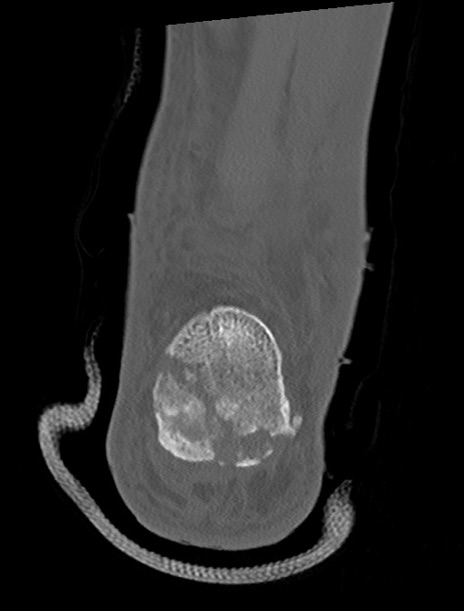

症例37 左足関節CT(冠状断像)

左足関節CT

矢状断像